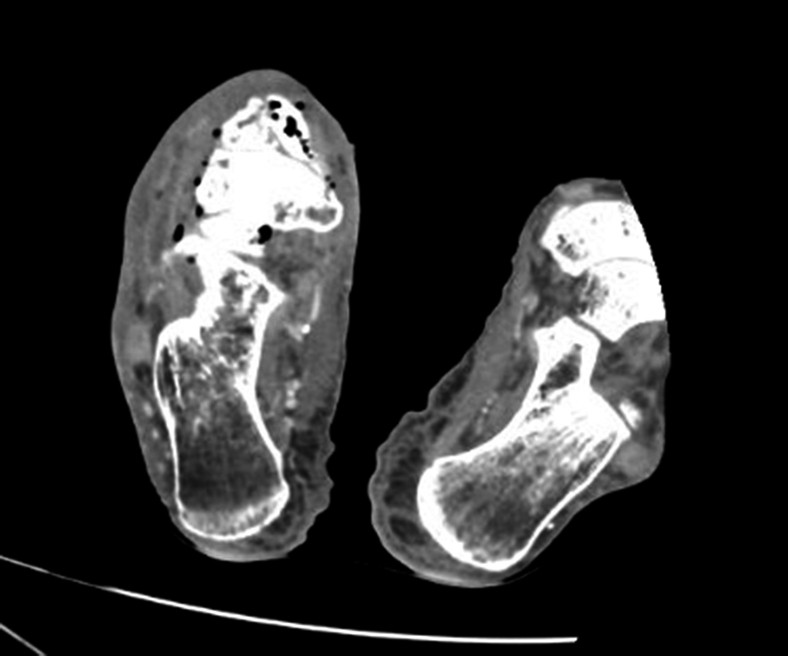

Clinical Images in Emergency Medicine: Man With Foot Pain and Indifference.

Alex Y Koo, Susan R O'Mara